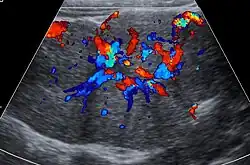

Ultrasound of malformed vessels within the fibrous scar of focal nodular hyperplasia.

Focal nodular hyperplasia's most recognizable gross feature is a central stellate scar seen in 60–70% of cases. Microscopically, a lobular proliferation of bland-appearing hepatocytes with a bile ductular proliferation and malformed vessels within the fibrous scar is the most common pattern. Other patterns include telangiectatic, hyperplastic-adenomatous, and lesions with focal large-cell dysplasia.[4] Rarely, these lesions may be multiple or can occur as part of a syndrome with hemangiomas, epithelioid hemangioendothelioma, hepatic adenomas, fibrolamellar hepatocellular carcinoma, vascular malformations of the brain, meningiomas, and/or astrocytomas.[4]